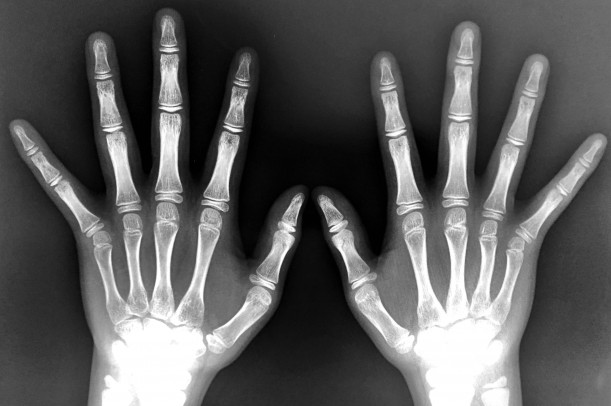

医療機関では、まず受傷の経緯を聞く問診と、腫れや変形の有無を確認する触診が行われます。

その後、必要に応じてレントゲン検査で骨折や脱臼の有無をチェックし、靭帯損傷の程度を確認することもあります。引用元:https://shinto-ort.com/finger

最近では、超音波(エコー)検査を使って腱の損傷や関節内の状態を細かく確認するケースも増えているそうです。

これらの検査を行うことで、「軽症か重症か」「どのくらい安静が必要か」が明確になり、無理のない施術計画を立てやすくなると言われています。